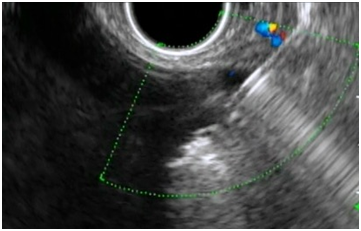

Figure 2A & 2B EUS images of the pancreatic pseudocyst.

Upon presentation to our hospital, he was complaining of intermittent abdominal pain, post prandial abdominal fullness, however he was not ill and abdominal examination showed distended abdomen with fullness of the left upper quadrant and scars of previous drain insertion. His investigations showed WBC 11.86, Hb 12.8 g/dl, Amylase 123, and Lipase 818. CT Abdomen showed a significant increase in the size of the pancreatic pseudocyst (8x8x12cm). Consent was obtained from his parents for EUS guided cystogastrostomy. Prophylactic antibiotic using Ciprofluxacin was given before and after the procedure for three days. The Olympus EVIS LUCERA Ultrasound Gastrovideoscope GF-UCT 260, 14.6 mm distal tip was introduced easily through the esophagus to the stomach. This showed a large homogenous cyst measuring 8X9 cm, with a clear wall that was adherent to the gastric wall with no intervening blood vessels. This was punctured with 19 G needle and 30 ml of clear aspirate was sent for chemistry and cytology. A guide wire with two loops was formed in the cyst over which a needle knife was used to puncture the gastric wall and create an opening which was dilated to 4 mm. Two pig tail stents 7 Fr 4 cm were placed to drain the cyst. Post drainage, he was doing well, with no signs of complications, and resolution of abdominal pain and distension. He continued to receive antibiotics and was discharge after 2 days of the procedure in a satisfactory condition. His amylase and lipase levels went down to 109 & 631 respectively. The amylase level in the fluid was 7425 u/l, normal CEA level and cytology showed cystic fluid with no malignant cells. Six weeks later, MRI showed complete resolution of the collection and a repeat EUS confirmed resolution of pancreatic pseudocyst. The stent was removed and currently the patient is well and asymptomatic (Figure 4).